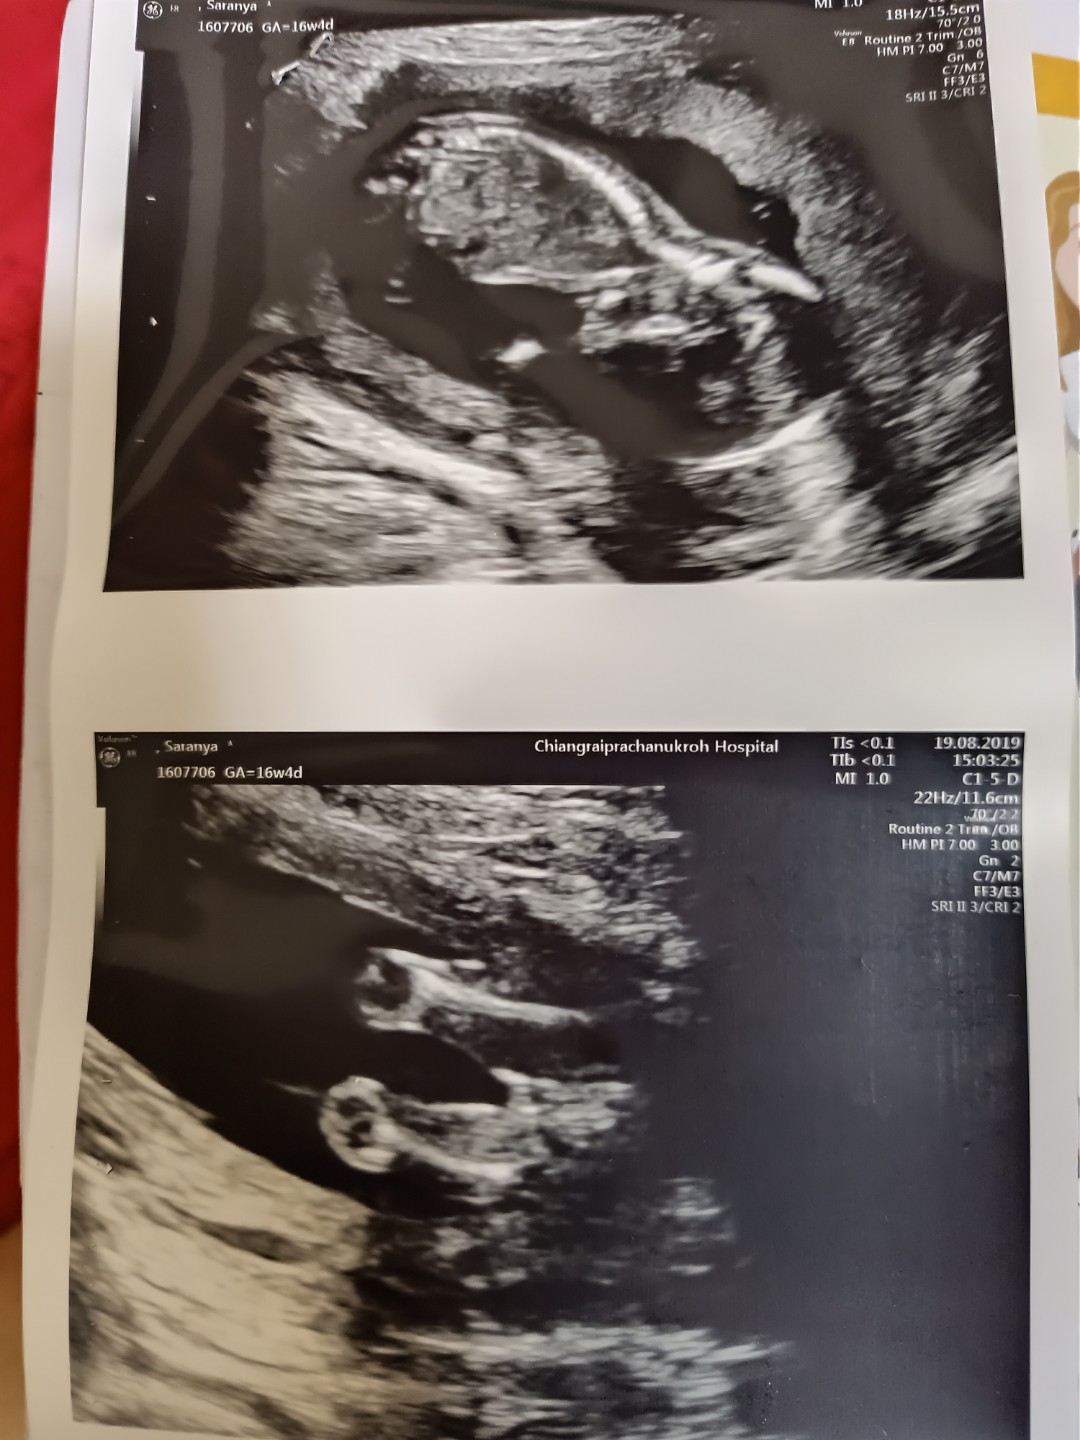

16w4d